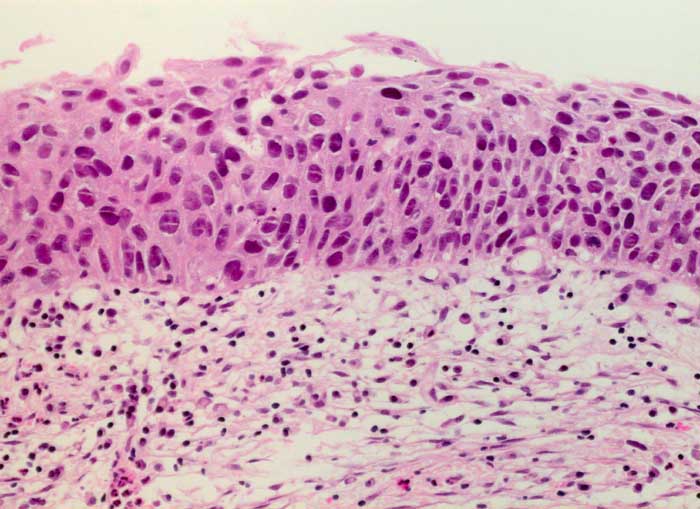

PathoPic – image database / PathoPic ID 6212 - schwere Dysplasie des Plattenepithels CIN III

schwere Dysplasie des Plattenepithels CIN III

Portio

Portiobiopsie: Hyperchromatische und unregelmässig gelagerte Plattenepithelzellen mit vergrösserten Kernen. Lediglich minimale Ausreifung.

Leicht blutende Ektopie.

Histologie

200